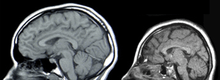

Neural scans of a normal-sized skull (left) and a case of microcephaly (right)